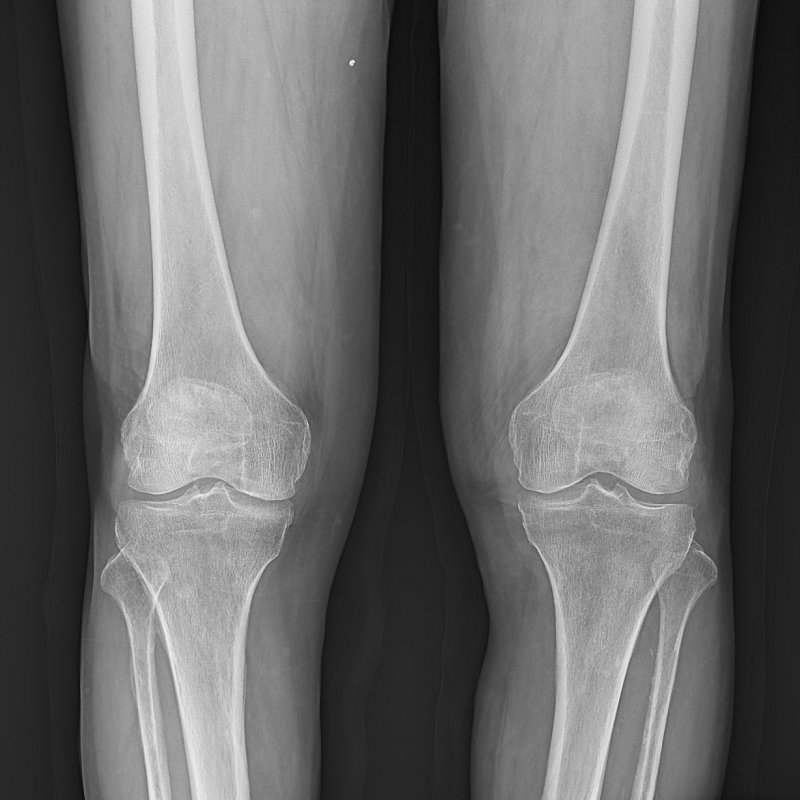

●呈現(xiàn)全下肢或全脊柱圖像

●在脊柱及下肢畸形矯正手術(shù)治療中,為術(shù)前方案制定和術(shù)后復(fù)查提供精準(zhǔn)測(cè)量

●有效解決傳統(tǒng)X光片不能一次成像問(wèn)題,為患者提供更加優(yōu)質(zhì)的醫(yī)療服務(wù)